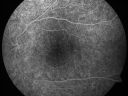

FLUORESCEIN ANGIOGRAPHY: The FA shows some irregular hyperfluorescence in the macula, which is mostly of a transmission than a blockage suggesting that there is some loss of pigmentation of the retinal pigment epithelium.